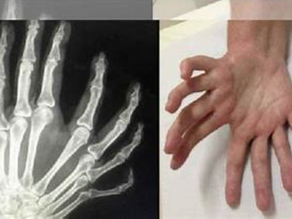

Ulnar Dimelia

Ulnar dimelia , also known as mirror hand, is one of the rarest hand deformities and occurs in approximately 1 in a million births....

incisionary

Jul 18, 20252 min read